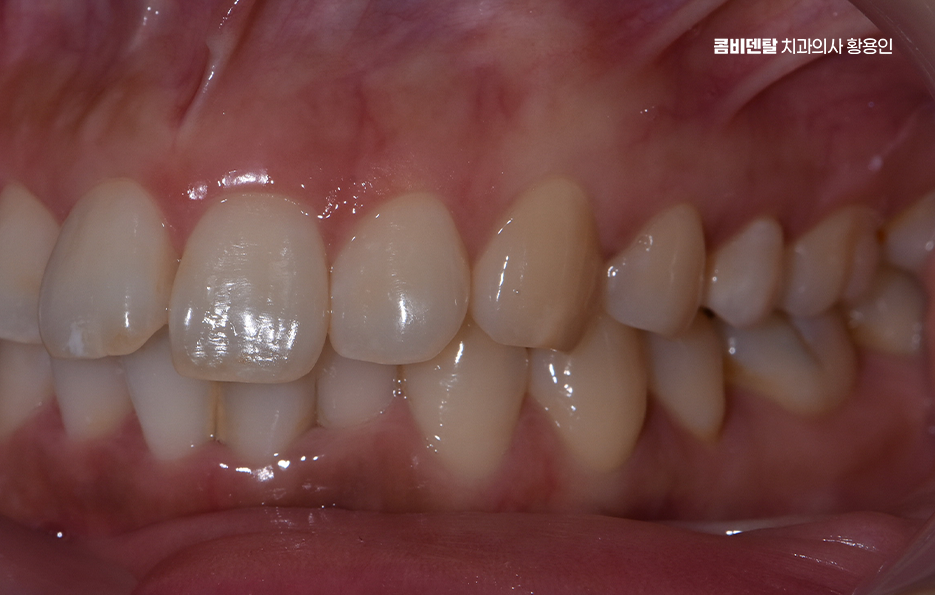

앞니 부분 교정이 가능한 대표적인 케이스로는 먼저 앞니 사이가 벌어진 ‘정중 이개’ 상태로 앞니 두 개 사이에 공간이 벌어져서 웃을 때 눈에 띄는 경우인데 이건 미세하게 치아를 당겨주거나 배열을 조정하는 것으로도 정리될 수 있어요.

또 하나는 앞니 한두 개가 뒤로 들어가 있거나, 다른 치아에 비해 튀어나온 경우로 이런 경우는 전체 교합에는 영향이 없지만 앞니 라인 자체가 삐뚤하게 보여서, 미소선이 비대칭으로 보이고 인상이 흐려지는 경우가 많은데 이런 경우도 앞니만 살짝 앞으로 빼주거나, 뒤로 넣어주는 방식으로 라인을 정리하면 인상이 부드러워 보이게 할 수 있어요.

앞니 부분 교정 가능한 다음 사례로는 치아가 겹쳐져 있는 경미한 부분 교차 교합인데 특히 아래 앞니 두세 개가 겹쳐 보이거나, 웃을 때 위 앞니 끝이 들쑥날쑥해 보일 때도 앞니 부분 교정으로 배열을 맞출 수 있으며 이런 경우는 부분 교정 만이 아니라 투명교정으로도 가능한 경우도 있어요

그런데 앞니만 건드리는 교정이라 하더라도 치아는 전체적으로 연결돼 있기 때문에, 단순히 눈에 보이는 앞니만 보고 ‘이건 부분 교정으로 되겠지’라고 판단하면 오히려 문제가 생길 수 있어서 앞니 부분 교정도 사전에 정밀한 진단이 필수이고 전체적인 교합 상태, 위아래 치열의 중심선이 맞는지, 앞니의 돌출 각도나 회전 상태, 잇몸뼈의 두께나 여유 공간 등을 모두 고려해서 가능 여부를 판단해야 하는 거예요